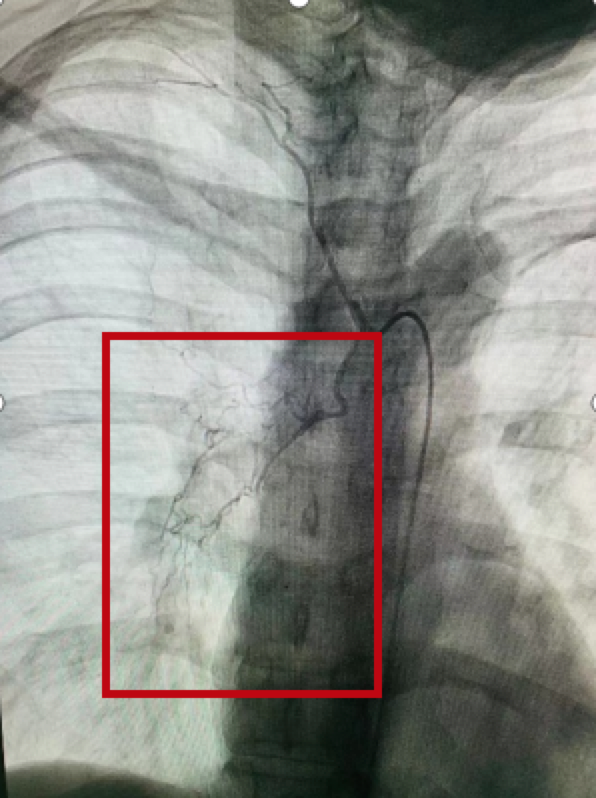

“医生,我还能不能有救了,我的孩子才5岁!”,上台前高女士哭着说,康凯医生握着患者的手说,“加油,你是最棒的妈妈!” 在紧锣密鼓的筹备下,高女士紧急上台行支气管动脉造影及栓塞术,术中发现右侧支气管动脉血管畸形,遂进行了支气管动脉栓塞术。术后,虚弱的她仍然存在呼吸困难,应用60%的高流量吸氧支持,专业的医护人员告知她如何进行体位引流,加强气道内陈旧血液的排出。

急诊手术的介入科刘增尧医师介绍说,大咯血患者如果未得到恰当处理的话,死亡率常在50%以上,死亡原因多为窒息和休克。多种肺部疾病可导致患者发生大咯血,其中肺结核和肺癌等是常见病因。一般来说,咯血量在医学上分三类,咯血量24小时超过500毫升为大量咯血,这位患者咯血量达到1000多毫升,且为支气管动脉出血,出血速度快,进展凶猛,处理不当,就会危及患者的生命。